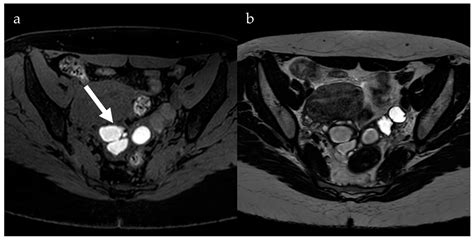

• Imaging Tests: Ultrasound, MRI, and CT scans can help detect endometrial tissue and monitor its progression.